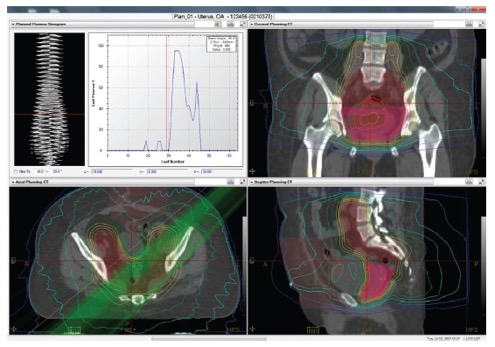

Το TomoTherapy σε συνεργασία με το σύστημα σχεδιασμού Precision™ και το σύστημα διαχείρισης δεδομένων iDMS™ της εταιρείας Accuray, ενσωματώνουν όλα τα απαραίτητα εργαλεία για την εκτέλεση προσαρμοζόμενων ακτινοθεραπευτικών πρακτικών.

Τα συγκεκριμένα συστήματα περιλαμβάνουν: λογισμικό για τον σχεδιασμό εξαιρετικά σύμμορφων και ομοιογενών δοσιμετρικών κατανομών, ενσωματωμένο αξονικό τομογράφο για καθημερινή λήψη εικόνων αξονικής τομογραφίας του ασθενούς, λογισμικό για την ευθυγράμμιση των καθημερινών εικόνων αξονικής τομογραφίας στις αρχικές εικόνες σχεδιασμού λαμβάνοντας υπόψη τις ανατομικές και βιολογικές μεταβολές του ασθενούς και δοσιμετρικό αλγορίθμο για τον υπολογισμό της δόσης στις καθημερινές εικόνες απεικονιστικής καθοδήγησης.

Οι ανατομικές και βιολογικές μεταβολές του ασθενούς (π.χ., απώλεια βάρους) κατά τη διάρκεια της ακτινοθεραπευτικής αγωγής λαμβάνονται υπόψη με το σύστημα PrecisesART.

Το σύστημα PreciseART δίνει την δυνατότητα στους ακτινοθεραπευτές Ιατρούς να παρακολουθούν την δοσιμετρική ακρίβεια στη χορήγηση της ακτινοθεραπευτική αγωγή και να επιλέγουν πότε απαιτείται αναπροσαρμογή του πλάνου θεραπείας.

Με τον τρόπο αυτό μπορούν να χορηγήσουν θεραπείες με υψηλή ακρίβεια σε κάθε ασθενή.

PreciseART:

- Αυτόματη επεξεργασία των καθημερινών εικόνων αξονικής τομογραφίας

- Παρακολούθηση της εκτέλεσης της χορηγούμενης ακτινοθεραπείας χρησιμοποιώντας κριτήρια ελέγχου και δράσης για κάθε κλινικό πρωτόκολλο

- Εργαλεία αυτόματης αναπροσαρμογής του πλάνου θεραπείας λαμβάνοντας υπόψη τις ανατομικές και βιολογικές μεταβολές του ασθενούς κατά την διάρκεια της ακτινοθεραπείας

- Ακριβή χορήγηση της συνταγο-γραφούμενης δόσης στον όγκο στόχο προστατεύοντας παράλληλα τους υγιής ιστούς από την πρώτη έως την τελευταία συνεδρία.